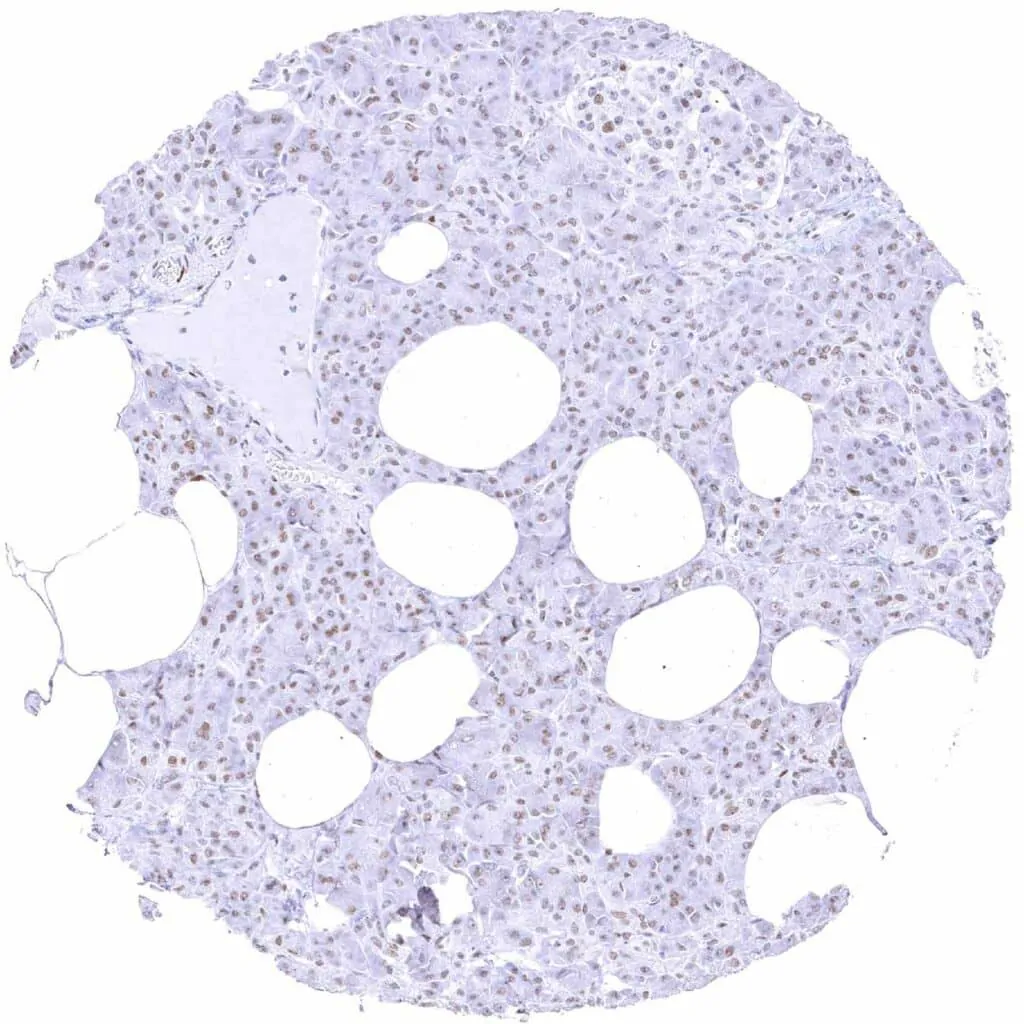

Thyroid gland – Weak TLE1 staining of follicular and endothelial cells